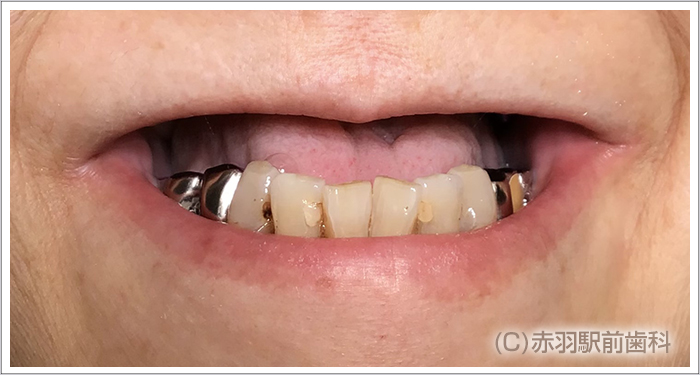

上顎の歯が3本しかない患者様です。 ![]()

上顎の歯は全て抜歯してインプラントを入れます。

固定式の上部構造ジルコニアセラミックを装着します。

笑っても上部構造の付け根は上唇の内側にありますから見える事はありません。 ![]() ![]()